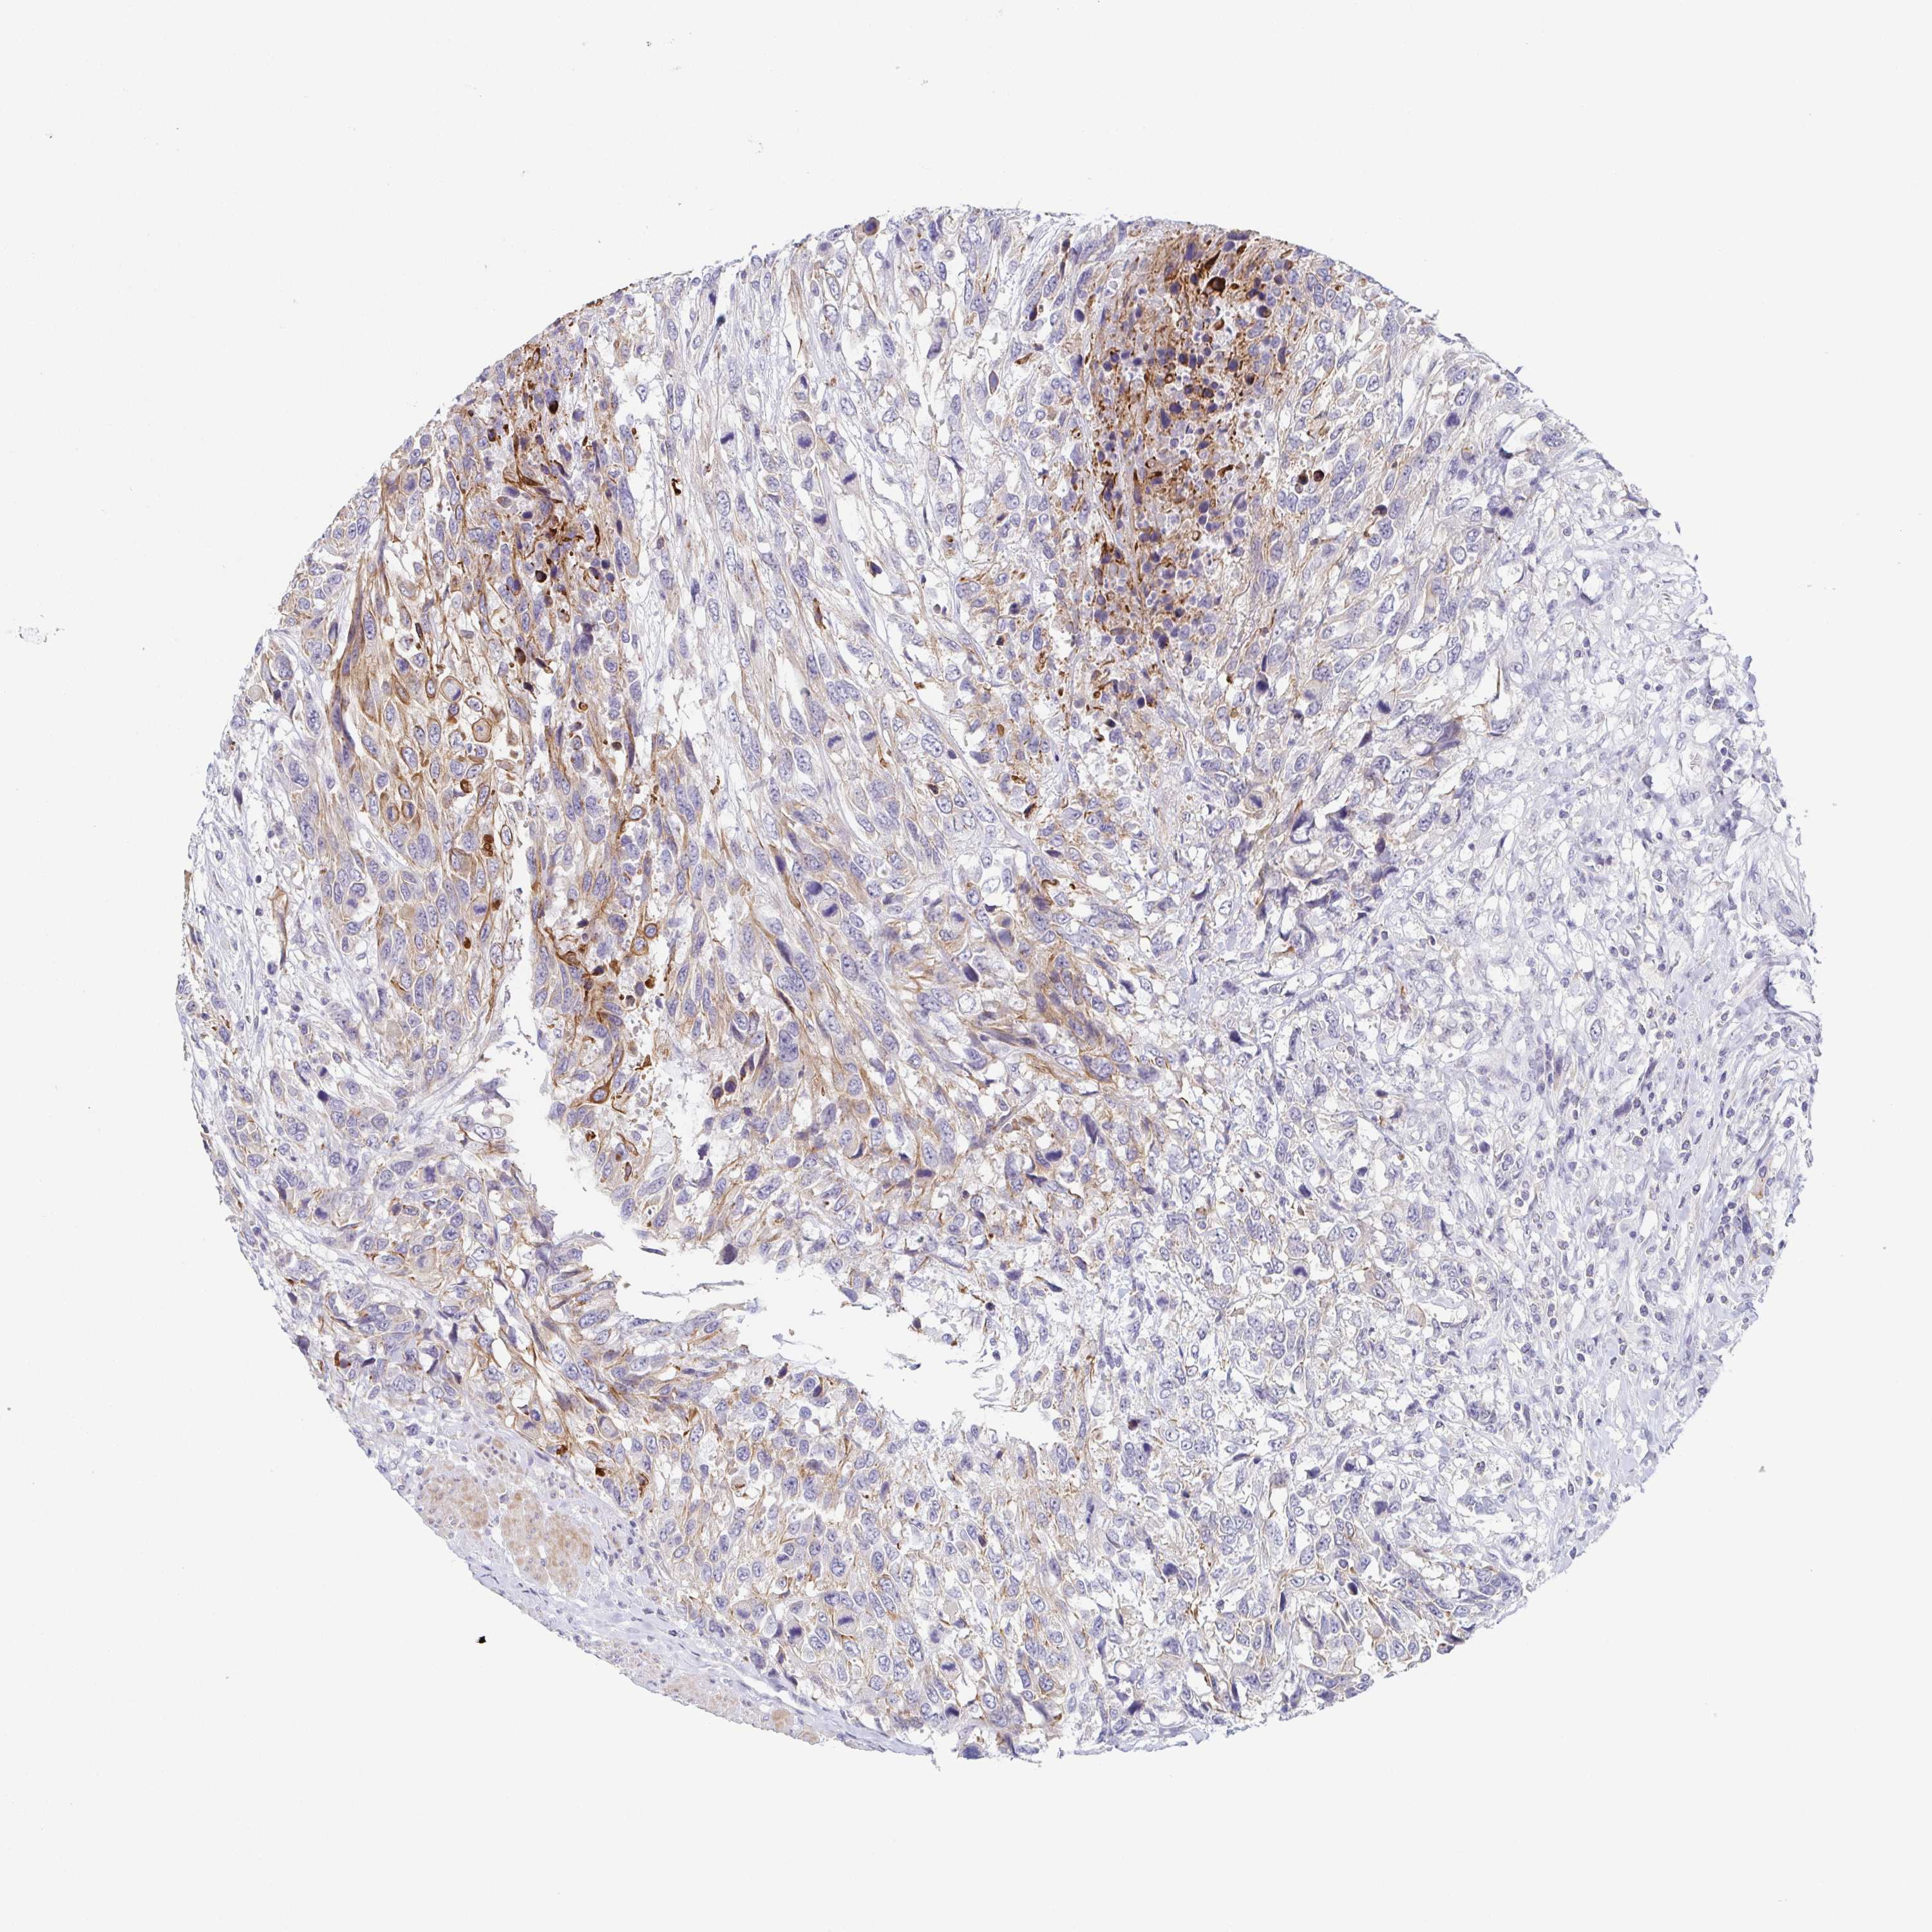

UROTHELIAL CANCER - Protein expressioni

A mouse-over function shows sample information and annotation data. Click on an image to view it in a full screen mode. Samples can be filtered based on level of antibody staining by selecting one or several of the following categories: high, medium, low and not detected. The assay and annotation is described here.

Antibody stainingi

Antibody staining in the annotated cell types in the current human tissue is reported as not detected, low, medium, or high, based on conventional immunohistochemistry profiling in selected tissues. This score is based on the combination of the staining intensity and fraction of stained cells.

Each image is clickable and will lead to virtual microscopy that enables deeper exploration of all samples and also displays staining intensity scores, fraction scores and subcellular localization as well as patient and tissue information for each sample.

Antibody HPA053343

Staining

High

Medium

Low

Not detected

Intensity

Strong

Moderate

Weak

Negative

Quantity

>75%

75%-25%

<25%

None

Location

Nuclear

Cytoplasmic/membranous

Cytoplasmic/membranous,nuclear

Urothelial carcinoma, High grade

Urothelial carcinoma, Low grade